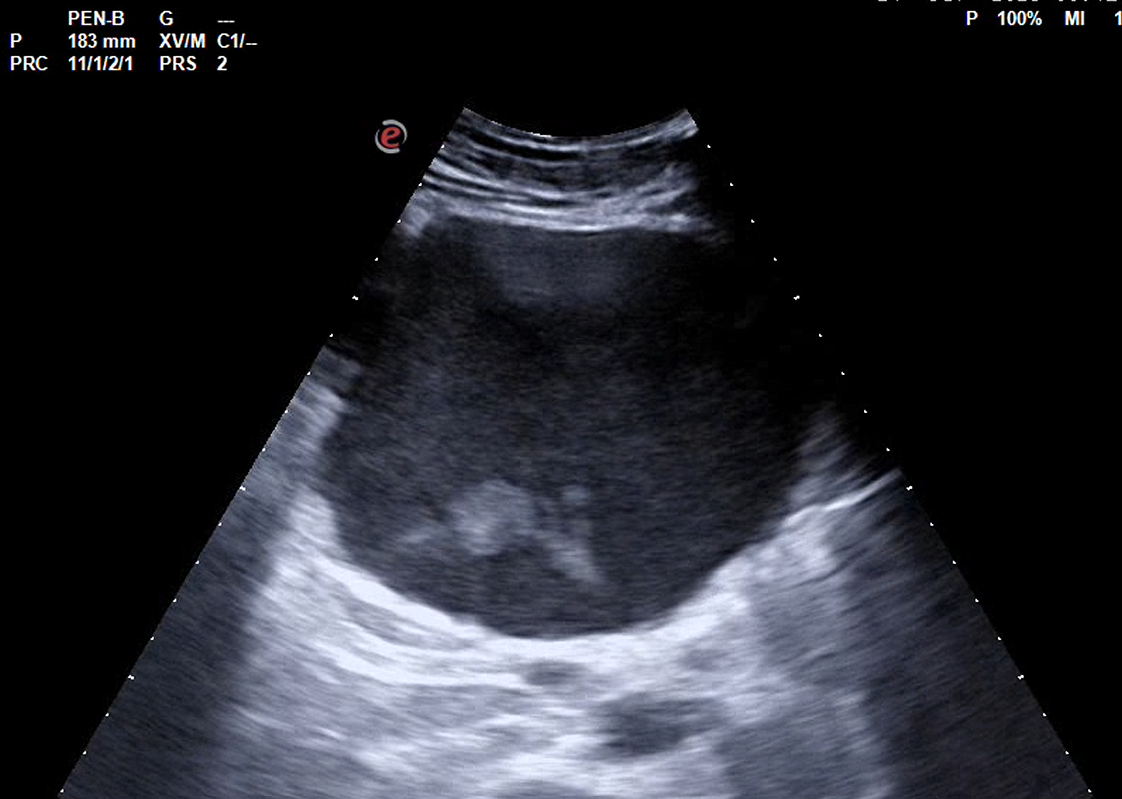

Realizamos ecografía abdominal en centro de salud, objetivándose grandes masas abdominales, no vascularizadas, de contenido hipoecogénico y heterogéneo, en todo el abdomen, sin distinguir si dependencia hepática o pancreática con leve dilatación de vía biliar intrahepática, vía extrahepática normal.